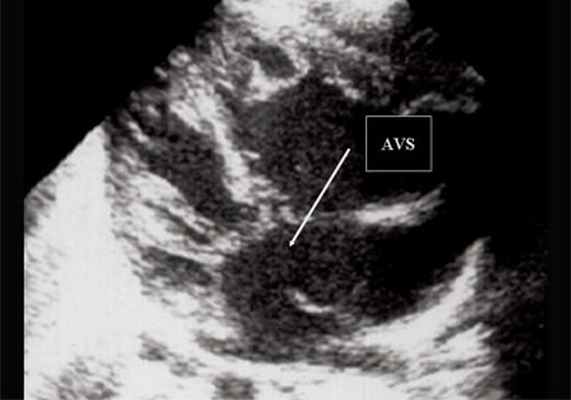

Рис. 5. Четырехкамерное сечение сердца плода. Стрелкой указан первичный дефект межпредсердной перегородки (АVS).